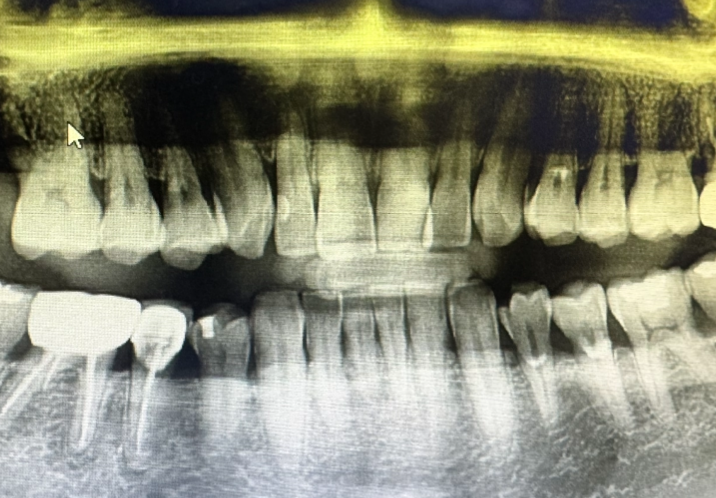

왼쪽위와 오른쪽위 치아 안쪽이 많이 노출된 상황으로 보인다거나 치석이 많이 끼는 형태의 치아이니 1년에 두 번 스케일링을 하는 것이 좋겠다는 치과의사의 의견을 들을 수 있어 치아관리에 매우 도움이 됩니다.